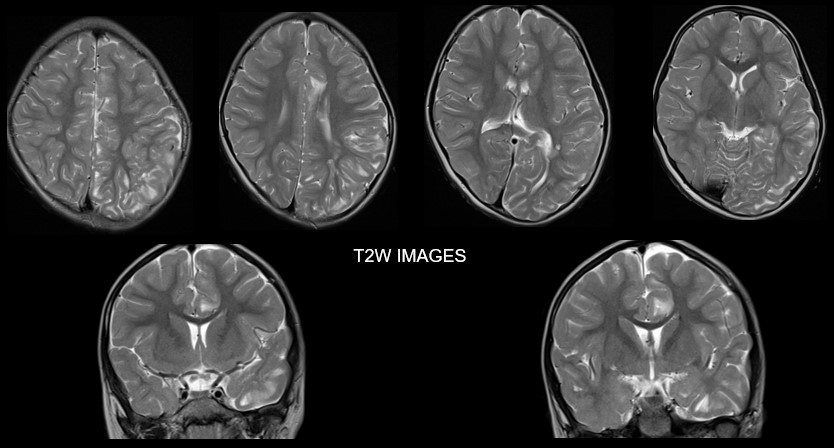

A. FINDINGS: MRI BRAIN WITH IV CONTRAST

• A. There is hemihemimegelencephaly in the left parieto-temporo-occipital lobes, characterized by enlargement of the involved hemisphere. There is associated gyral thickening with white matter signal changes in the adjacent subcortical white matter.

• B. Areas of rarefaction are seen in white matter signal changes. Note is also made of periventricular nodular heterotropia along the atrium of the left lateral ventricle.

• C. No volume loss in bilateral cerebellar hemispheres. No abnormal post-contrast enhancement.

Left posterior quadrantic dysplasia with associated subcortical white matter signal abnormalities and periventricular nodular heterotropia.